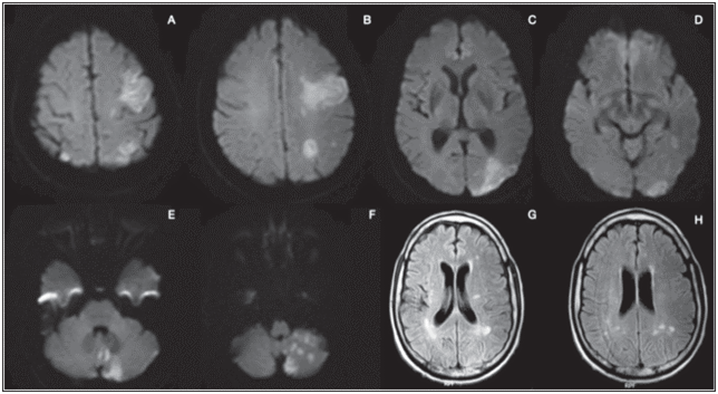

Figura 1 Caso 1. Resonancia magnética cerebral simple en ventana DWI (A, B y C) y T2 FLAIR (D y E) se evidencian áreas de infarto hiperagudo en lóbulo frontal izquierdo y lacunar talámico derecho.

Hombre de 50 años con antecedente de hipertensión arterial quien ingresa a urgencias con cuadro de dos horas de evolución de hemiparesia derecha y disartria con NIHSS de ingreso de ocho, signos vitales: tensión arterial 190/100 mmHg, frecuencia cardiaca 80 lpm, frecuencia respiratoria 23 rpm, SaO2 83% y glucometría en 382 mg/ dL; es llevado a RMN cerebral simple con evidencia de restricción en la difusión del tálamo derecho y frontal izquierdo no evidente en Flair (Figura 1). Se inicia manejo con la labetalol logrando control de presión arterial, se procede a trombolisis con rTPA/alteplasa, a las 24 horas con NIHSS de 1. La radiografía de tórax de ingreso evidencia infiltrados difusos en ambos campos pulmonares compatibles con infección por COVID-19. RT PCR para SARS-CoV-2 inicial negativa, por lo que ante alta sospecha clínica al día siguiente se realiza prueba confirmatoria con resultado positivo. Se realiza diagnóstico de diabetes mellitus por HbA1C 10%. En la pesquisa neurovascular se realiza Doppler de vasos de cuello, electrocardiograma y ecocardiograma los cuales se encontraban dentro de límites normales. Luego de cinco días de hospitalización presenta dolor torácico de característica pleuríticas asociado a diaforesis y desaturación por lo cual se toma electrocardiograma con evidencia de taquicardia sinusal, troponina negativa y angioTAC evidenciando tromboembolismo pulmonar agudo bilateral a nivel del lóbulo inferior izquierdo y lóbulo superior derecho (Figura 2). Luego de 18 días de hospitalización se da egreso con única secuela neurológica mono hipoestesia de miembro superior derecho con oxígeno por cánula nasal a dos litros.

Figura 3 Caso 2. RMN cerebral simple en ventana DWI (A - F) se evidencian infartos fragmentados de evolución hiperaguda, cortico-subcorticales de predominio izquierdo y cerebeloso. Ventana T2 (G y H) con compromiso bilateral sin componente hemorrágico.

Hombre de 47 años con antecedente de hipertensión arterial y diabetes mellitus no insulino requiriente quien ingresó al servicio de urgencias luego de dos horas de haber presentado episodio convulsivo tónico clónico con recuperación parcial del estado de conciencia y hemiplejia izquierda de novo. Signos vitales de ingreso con TA 153/90 mmhg, Fc 100 lpm, Fr 30 rpm, SaO2 70% con glucometría de 250 mg/ dL. Se realiza TAC de cráneo simple con hipodensidades focales córtico subcorticales frontal alta izquierda y occipital ipsilateral en relación con eventos isquémicos agudos sin presencia de sangrado, por lo que se realiza RMN cerebral simple con evidencia de infartos fragmentados hiperagudos cortico subcorticales en múltiples territorios arteriales (Figura 3). NIHSS de ingreso 23 puntos por lo que se realiza trombolisis con rTP alteplasa con NIHSS posterior de 21, declarándose como trombólisis fallida. Se toma RT PCR para COVID con resultado positivo.